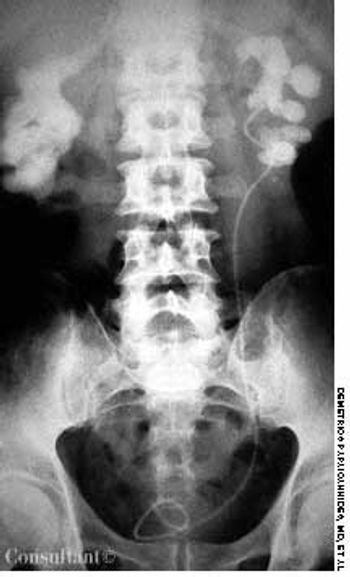

A roentgenogram of the kidneys, ureter, and bladder of a 58-year-old man shows bilateral stones in the renal pelvis and the renal calyces. The patient had a history of recurrent urinary tract infections caused by Proteus mirabilis. A ureteral catheter (pigtail) had been placed in the pelvis of the left kidney to facilitate drainage.